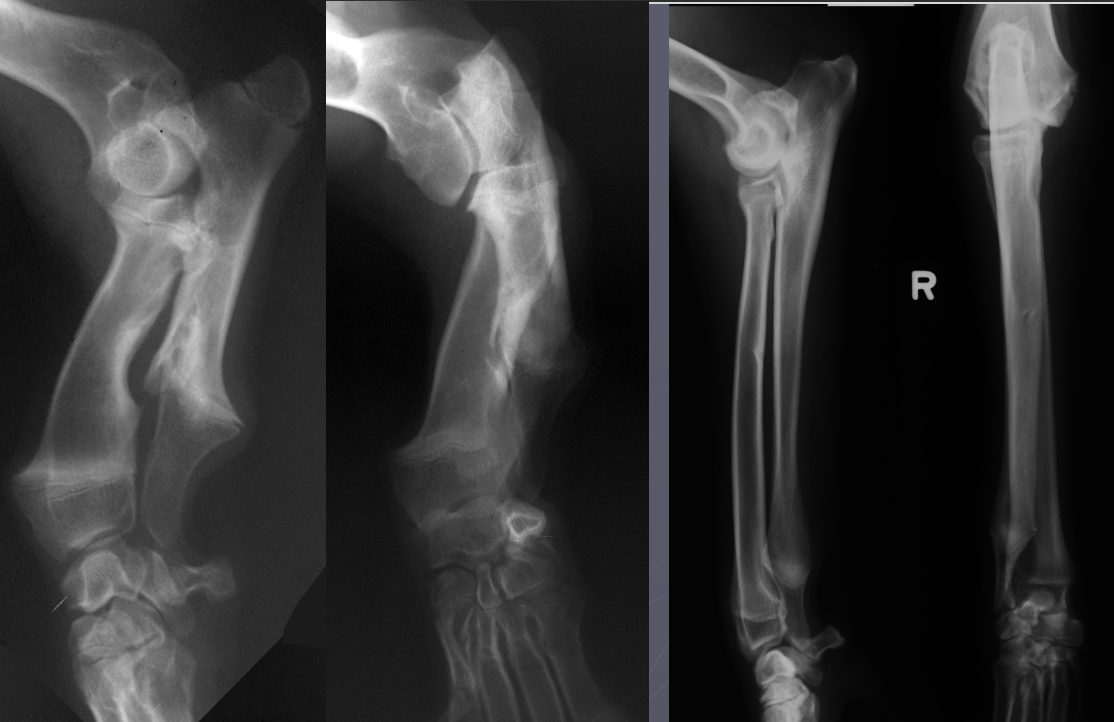

What is shown in this radiograph?

premature distal ulnar physis closure

-bowing of radius

widening of humero-ulnar joint space due to premature distal ulnar physis closure

widening of humero-ulnar joint and secondary UAP due to premature distal ulnar physis closure

What is shown in these radiographs?

premature distal radial physis closure

-increased radiocarpal joint space

-increased humero-radial joint space

Which physis has closed prematurely in each set of radiographs?

Left: distal ulnar physis

Right: distal radial physis